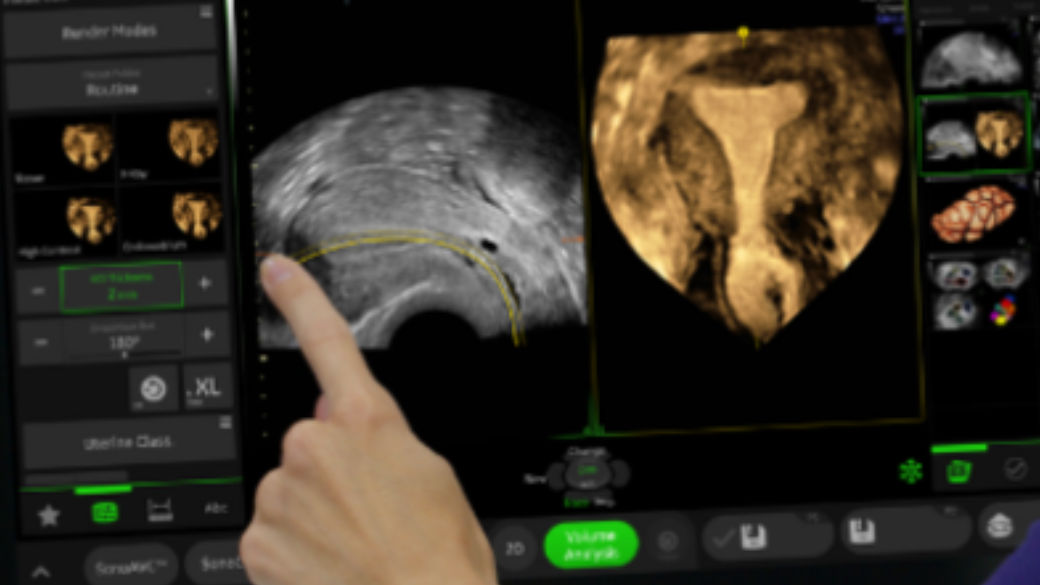

AI screening assistant for fetal heart and brain

Fetoly is the first real-time AI solution for fetal ultrasound, helping to ensure a complete and standardized examination. Integrating with most ultrasound systems, it provides instant feedback to help diagnostic confidence and help improve pregnancy outcomes.

• Instantly detects over 100 key fetal structures

• Automatic freeze and view selection

• Real-time ratios supporting the detection of pathologies